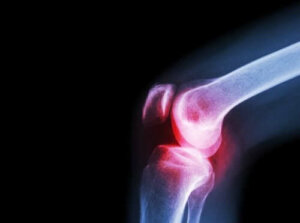

Çoğu septik artrit vakasına bakterilerin, özellikle stafilokok ve streptokokların neden olduğunu belirtmek önemlidir. Her yaşta ortaya çıkabilmekle birlikte en sık olarak bebeklerde görülürler. Dahası, esas olarak kalçayı ya da dizi etkilerler.

Ardından, doktorlar etkilenen eklemin bir röntgenini de çekebilirler. X ışınları ve diğer tanısal görüntüleme araçları hasarı değerlendirmeye yardımcı olabilir.